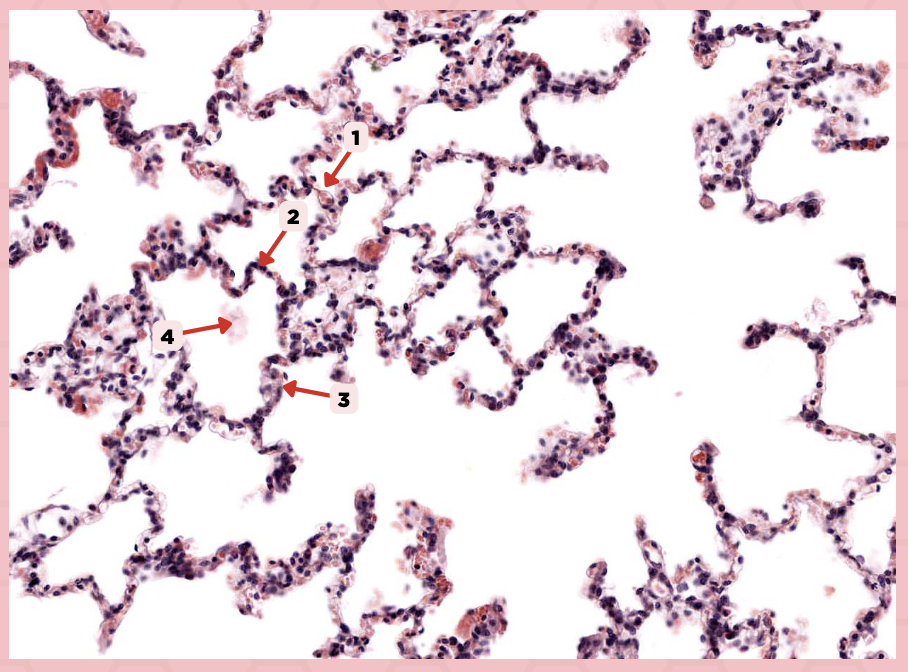

Lumens and Interalveolar septa

Name the irregular spaces and the fine threads of tissue that separate them.

Interalveolar septa

Identify the structure labeled as 1.

Type 1 and Type 2 Alveolar Cells

What are the 2 cell types for alveoli?

Simple squamous epithelium

What kind of epithelium are these alveolar cells?

Interalveolar septum

Identify the structure labeled as 1.

Type I alveolar cell

Identify the structure labeled as 2.

Type II alveolar cell

Identify the structure labeled as 3.

Pulmonary Alveolar Macrophages (Dust Cells)

Identify the structure labeled as 4.

Pulmonary Alveolar Macrophages (Dust Cells)

What are the most numerous cells inside the alveoli?

Pneumocyte Type I

Which of the following labeled structures covers 95% of the alveolar surface?